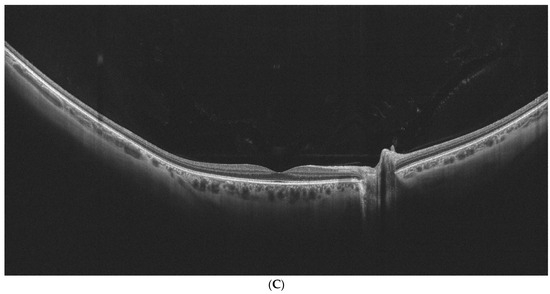

Figure 2A–C show examples of UWF-OCT images of AMD and healthy patients.

Figure 2.

(A) is an example of UWF-OCT in geographic atrophy. Increased penetration of the retina is noted in the central part of the posterior pole. The choroid is distinctly thin. Retinal thickness values state 284 µm, 312 µm, and 227 µm respectively for the central, perifoveal, and peripheral zones. For the choroid, these thicknesses constitute 184 µm, 174 µm, and 152.75 µm, respectively. (B) Exudative form of AMD in UWF-OCT scan. Subretinal and sub-RPE fluid is observed in the retinal center. As in the previous scan, the choroid appears thin. Retinal thicknesses are observed at 345 µm in the central zone, 266.81 µm for the perifoveal, and 206 µm for the peripheral. Choroidal thickness values stand for 223 µm, 168.25 µm, and 139.25 µm, respectively, for the analyzed sectors. (C) UWF-OCT scan in a healthy individual. The choroid is apparently thicker compared to patients with AMD from (A,B). Retinal thickness measurements are noted at 351 µm, 299 µm, and 216.5 µm for central, perifoveal. and peripheral zones, respectively. Choroidal thickness values for these zones are, respectively, 398 µm, 328.87 µm, and 252.37 µm.